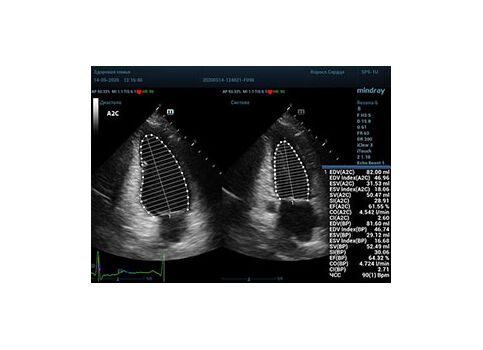

Что могут предложить современные приборы? Приборы нашего времени являются мощными вычислительными машинами, способными обрабатывать полученную информацию даже без помощи человека. Система автоматического вычисления фракции выброса – AUTO EF на приборах серии Resona компании Mindray сделает все за вас. За пару секунд прибор сам отыщет нужную фазу сердечного цикла и произведёт измерение и расчеты, а также покажет график изменения объема в сердечном цикле. От Вас требуется только получить качественное 4С и 2С сечение. Впрочем, прибор всегда оставляет возможность коррекции, если доктор имеет свое мнение на расположение точек планиметрии или момента измерения по ЭКГ каналу.